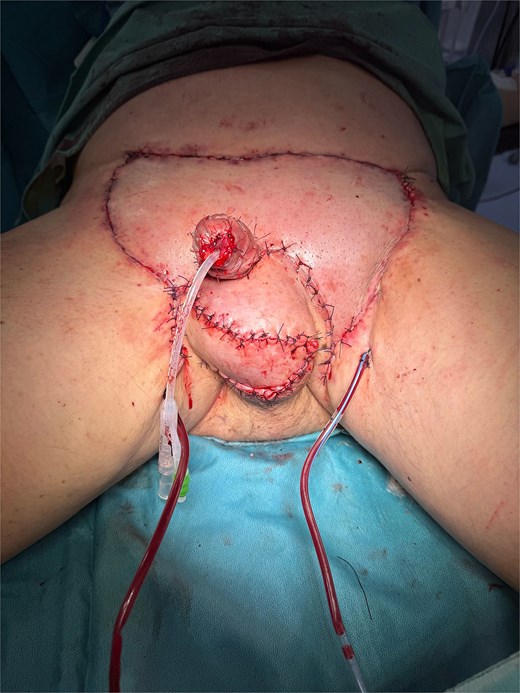

An en-bloc excision of all affected skin was performed, maintaining a minimum safety margin of 10 mm around each suspicious lesion (Fig. 3), exposing the testes and the spermatic cords, which were preserved. The scrotal dissection extended to the inguinal and perianal regions. The penile skin was incised dorsally in a book-like fashion down to the dartos fascia, then continued laterally and ventrally, with careful preservation of the urethra and its continuity with the scrotal skin. A glansectomy was then performed. Subsequently, the scrotum was reconstructed using double-opposing Singapore flaps, while penile reconstruction involved a lower abdominal Keystone flap for the base and a split-thickness skin graft for the shaft (Fig. 4).

The patient had an uneventful postoperative course. The only complication was partial necrosis of the distal portion of the Singapore flap. This area healed by secondary intention under conservative management. At one and a half months, the surgical site was completely healed (Fig. 5). No urinary symptoms were reported, and spontaneous erectile function of the penile stump was preserved. However, reduced sensitivity and a mild deformity during erection were noted.